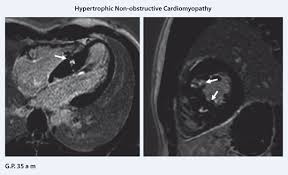

Myokarditis Kardio Mrt / Kardiale Magnetresonanztomografie Bei Herzinsuffizienz Kardiologie Gefassmedizin Universimed Medizin Im Fokus : Myokarditis fulminant akut chronisch aktiv chronisch persistierend.

Myokarditis Kardio Mrt / Kardiale Magnetresonanztomografie Bei Herzinsuffizienz Kardiologie Gefassmedizin Universimed Medizin Im Fokus : Myokarditis fulminant akut chronisch aktiv chronisch persistierend.. Myocarditis in patients with clinical presentation of myocardial infarction and normal. Myocarditis, also known as inflammatory cardiomyopathy, is inflammation of the heart muscle. Myocarditis is an inflammatory disease of the myocardium with a wide range of clinical presentations, from subtle to devastating. Ein in der mrt nachweisbares lge ist dabei nachweislich mit einer ungünstigeren prognose und einer erhöhten rate kardialer ereignisse assoziiert. Chend der definition der weltgesund unterdrückung ermöglichen.